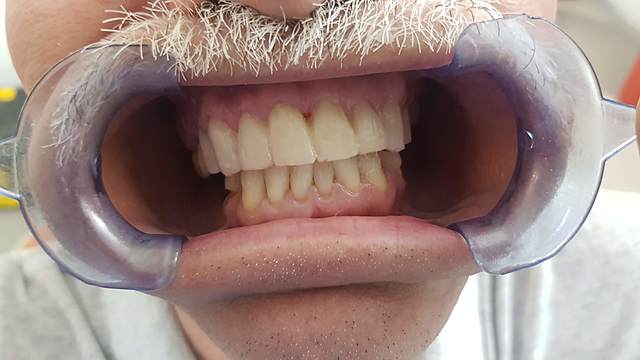

• Mock up

Mock up

En esta cita se realiza un mock up con bisacryl, que sirve para tener un estimado de la altura, mordida y abultamiento de los dientes.

• Ajuste de la oclusión, rebase y toma de modelos

Ajuste de la oclusión, rebase y toma de modelos

Se realizó pulido y recordado de los abultamientos, adelgazando el grosor del material, se tocaron los puntos de oclusión y se realiza la confección del material de rebase, se tomaron modelos para mandar a elaborar prótesis parcial removible temporal

• Cementación de coronas de zirconia

Se recibirán las coronas de zirconia y posteriromente se prueban y si no se detecta ningún problema se cementan las coronas con los protocolos adecuados.